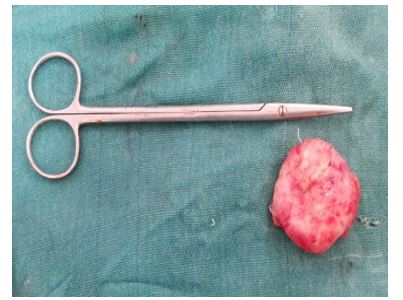

Kumar et al. [12] reported a 31-year-old lady who had presented with a gradually progressive, painless lump within her right breast over a period of one year. She did not have any past medical history of injury, discharge from her nipple, or a family history of carcinoma of the breast. She was a housewife who did not disclose having had any close contact with any animal. She was found upon examination to have a non-mobile, firm lump that measured 5 cm x 5 cm within the sub-areolar region of her right breast which was predominantly located within the upper quadrants of the breast. The nipple of her right breast was noted to be retracted. The left breast and nipple were found on examination to be normal and there was no evidence of axillary or cervical lymph adenopathy. She had mammogram which showed a large, smooth walled, well-defined, opacity in the right sub-areolar region (see figure 7). The left breast was normal. She had ultrasound scan of her breasts which showed a thick walled cystic lesion with floating membranes as well as internal echoes within the sub-areolar region of her right breast. She also had chest x-ray and ultrasound scan of her abdomen and which were normal. She underwent excision of the right breast lump in which the right breast lump was removed completely via a curvilinear incision just above the areolar margin (see figures 8 and 9). The excised cyst was found on gross examination to be oval in shape and it had measured 5 cm x 4.5 cm x 3 cm. upon opening of the cyst, endocysts were visualised which did confirm that the cyst was a hydatid cyst (see figure 10).